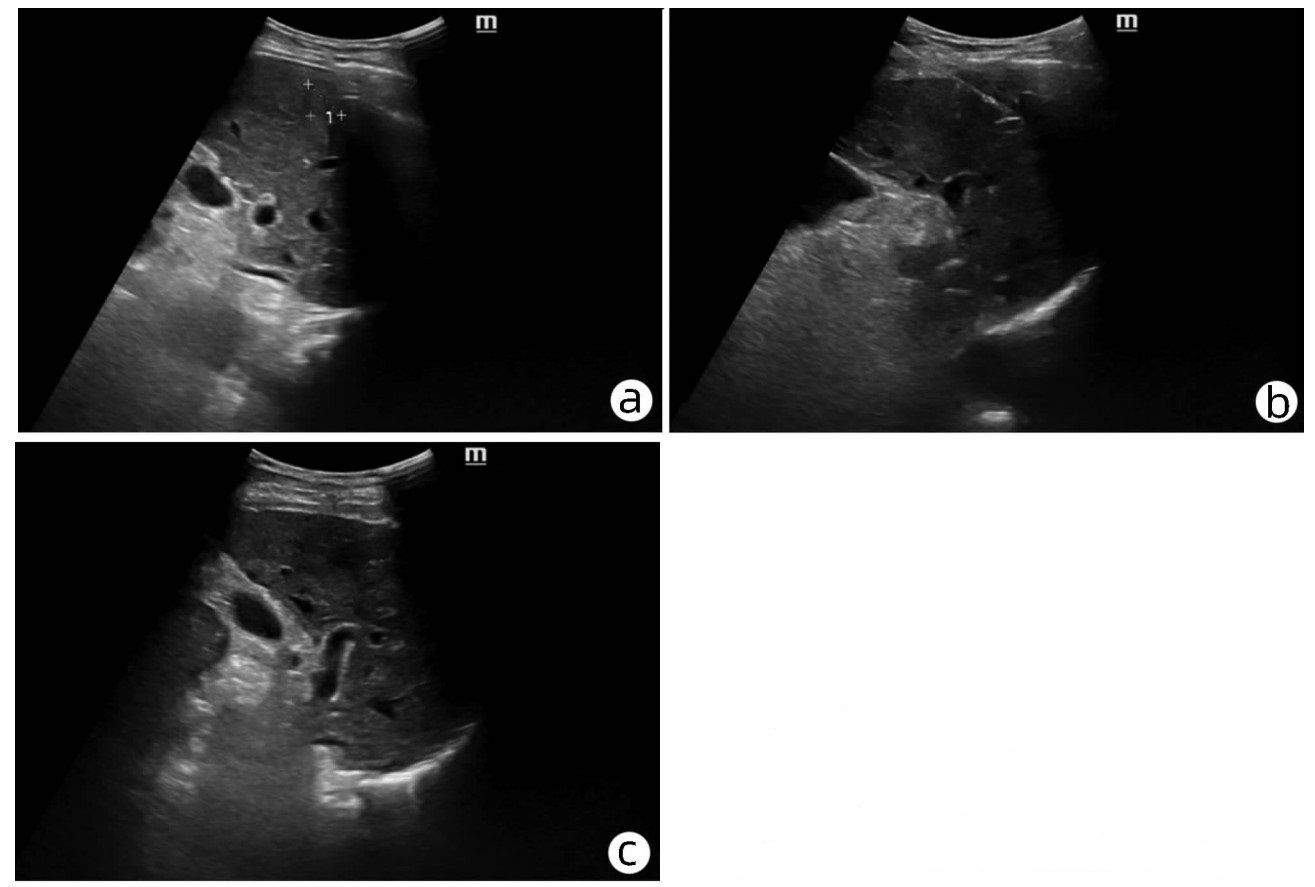

Late-onset diaphragmatic hernia after microwave ablation of hepatocellular carcinoma: A case report

Xiaodong WANG, Yurong ZHANG, Xiaoning ZHU, Ding ZHENG, Jing WANG

2022, 38(8): 1875-1877. DOI: 10.3969/j.issn.1001-5256.2022.08.029

Abstract(834) HTML (321) PDF (2572KB)(47)

Abstract: